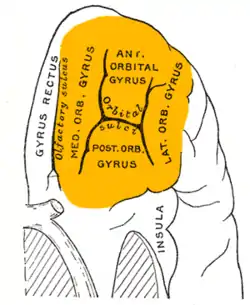

Orbital surface of left frontal lobe. Orbital gyri shown in orange. | |

The inferior or orbital surface of the frontal lobe is concave, and rests on the orbital plate of the frontal bone. It is divided into four orbital gyri by a well-marked H-shaped orbital sulcus. These are named, from their position, the medial, anterior, lateral, and posterior, orbital gyri. The medial orbital gyrus presents a well-marked antero-posterior sulcus, the olfactory sulcus, for the olfactory tract; the portion medial to this is named the straight gyrus, and is continuous with the superior frontal gyrus on the medial surface.